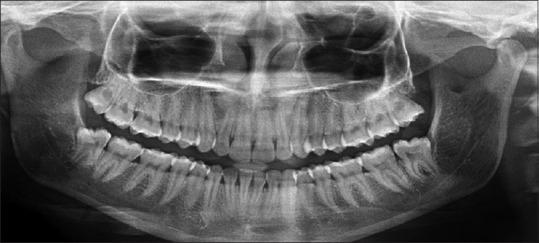

This split-mouth prospective trial constituted prophylactic removal of M3Ms with Sticky bone grafted in the study site as a primary predictor variable. Patients underwent 3 months of mandatory follow-up where pain, swelling, interincisal mouth opening, and gingival healing were measured on the 3, 7, and 14 day using the Numeric Rating Scale, anatomic landmarks, steel metric ruler, and criteria given by Landry . respectively. Radiological healing was calculated based on the height of the socket, Kelly's Index, and histogram values immediately after the procedure at 1 week, 1 month, and 3 months, respectively. Statistical comparison was made using Paired -test. < 0.05 was considered significant.

本双盲前瞻性试验将在研究部位植入粘性骨预防性拔除M3M作为主要预测变量。患者接受3个月的强制随访,分别在第3、7和14天使用数字评分量表、解剖标志、钢尺以及兰德里给出的标准测量疼痛、肿胀、切牙间开口度和牙龈愈合情况。分别在术后即刻、1周、1个月和3个月根据拔牙窝高度、凯利指数和直方图值计算放射学愈合情况。采用配对t检验进行统计学比较。P<0.05被认为具有显著性。